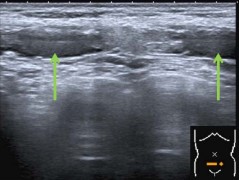

An ultrasound (US) of the lower abdomen was performed, to see whether there was a herniation of the abdominal wall, a rectus hematoma, or even a rupture of the abdominal muscle.

The US showed a partial rupture of the rectus abdominis muscle at both sides of the linea alba (Figures 1-3).

The rupture was approximately 1cm wide and 0.6cm deep. At the ventral side of the abdominal wall, muscle fibers were undamaged and the linea alba was intact. No intramuscular hematoma was seen.

Figure 1: Rupture in the right abdominal muscle.

Figure 2: Rupture in both abdominal muscles.

Figure 3: Rupture in the left abdominal muscle.

In the ED the rupture was diagnosed by US. Compared to MRI, US is less invasive, well tolerated and cost-effective [20-21]. In contrary, its contrast is not as good as MRI.